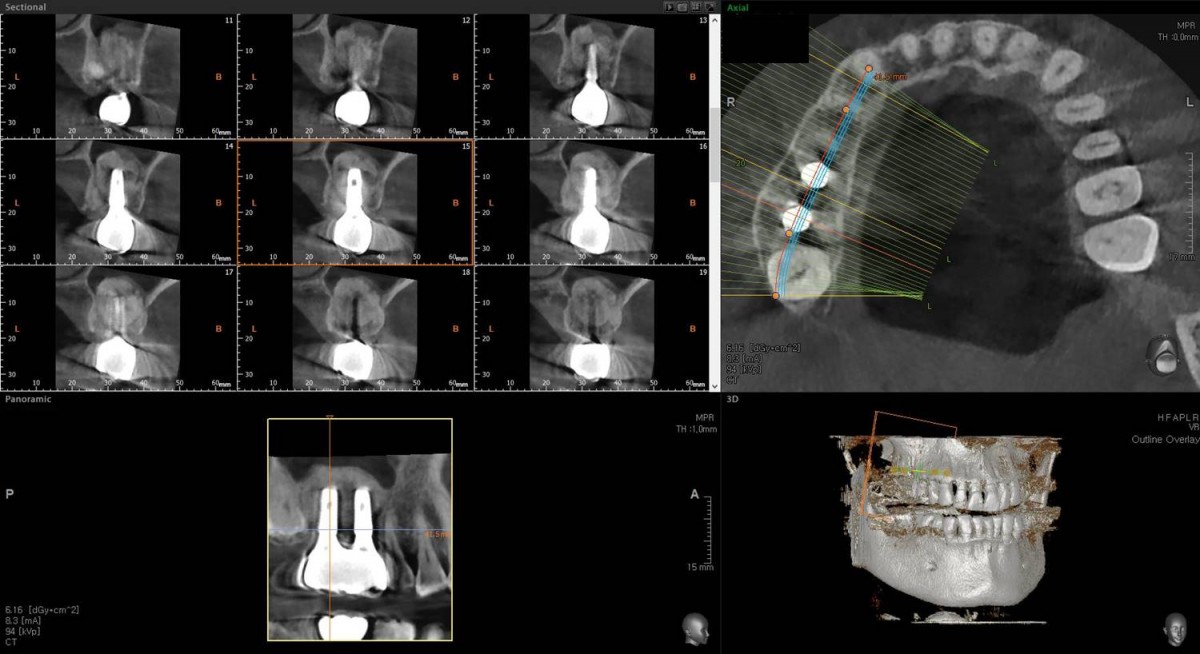

Maxillary Sinus Graft, 2 Implants, Crown Contouring

<GCaks> A 56-year-old male patient had pain-inducing caries, and perio-involved tooth mobility resulted in a tooth fracture at 1st molar. And it was removed months ago. He was a heavy smoker and showed poor oral hygiene.